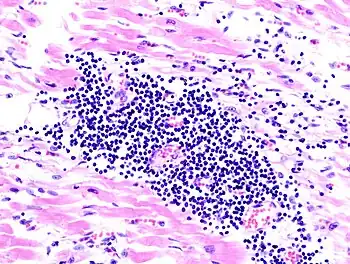

- Hematopathology (A board-certifiable subspecialty in the U.S.)